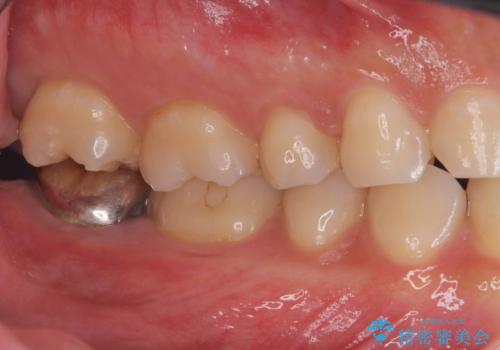

- 「銀歯を白くしたい」を主訴に来院された患者様です。

銀歯と虫歯を除去後、オールセラミッククラウンで治療を行いました。

銀歯を除去後、オールセラミッククラウンで治療を行いました。

根管治療はご希望されなかったため被せ物のみ治療しています。

クリアランスが少なかったため支台歯の真ん中に保持溝を入れています。